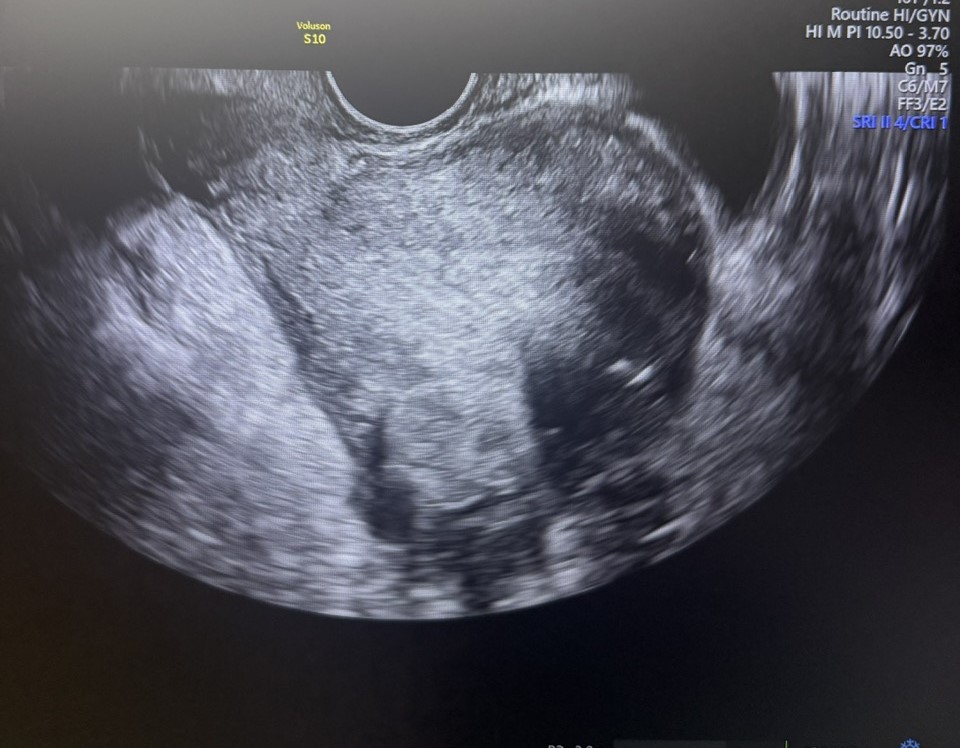

38-летняя пациентка обратилась в ГКБ им. В.В.Вересаева с жалобой на увеличение размеров живота. Внешне это выглядело так, будто женщина находится на 6 месяце беременности. Причиной оказалась множественная миома матки гигантских размеров – сразу несколько миоматозных узлов, один из которых достигал 20 сантиметров в диаметре.

После тщательной предоперационной подготовки пациентке была выполнена срединная лапаротомия. Во время операции выяснилось, что увеличенная матка буквально заполняет весь малый таз и часть брюшной полости. В ней располагались как субсерозные, так и интрамуральные миоматозные узлы, а также было обнаружено доброкачественное образование правого яичника.

Специалисты последовательно удалили четыре миоматозных узла, включая гигантский узел размером 20×15 см.